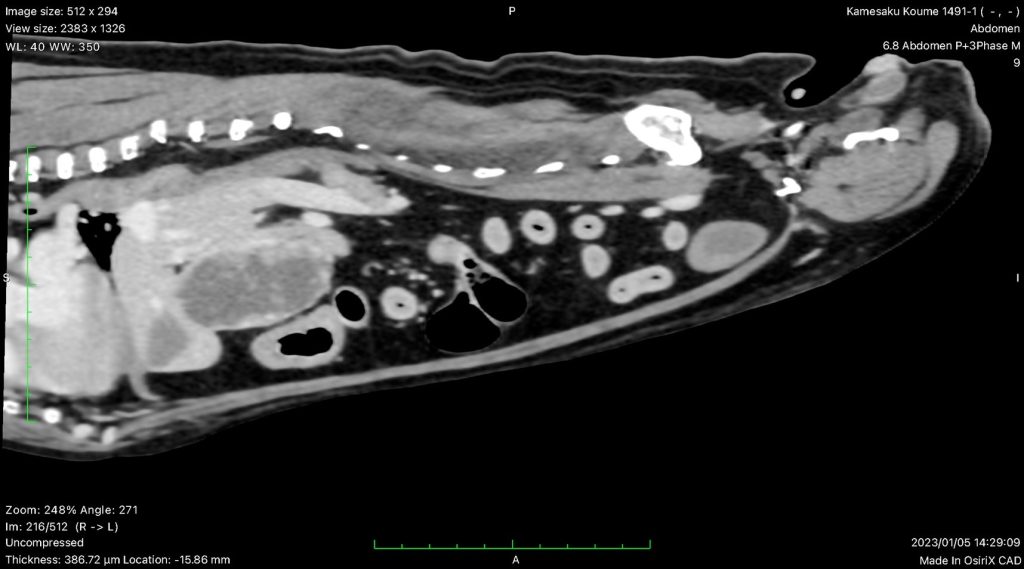

- 腹腔内のがん(肝細胞癌、腺癌、血管肉腫、GIST、副腎腫瘍、消化管型リンパ腫など)

がんの診療では、まず腫瘍の種類や状態を詳しく把握することが重要です。腫瘍そのものの検査に加え、転移の有無を確認するために全身の検査を行います。

- 術前CT検査